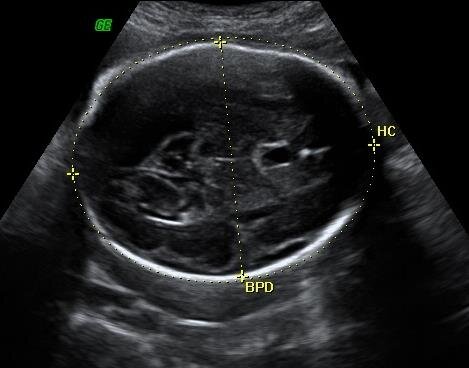

No caso da estimativa de peso por ecografia, trata-se de um peso estimado com base em parâmetros ecográficos, habitualmente o perímetro cefálico, diâmetro biparietal (largura da cabeça), perímetro abdominal e comprimento do fémur. Estes parâmetros são usados em uma de dezenas de fórmulas publicadas (mais frequentemente uma de um autor chamado Hadlock) e o resultado é um valor estimado de peso. Este resultado é naturalmente falível, e o erro associado pode ser verificado nos artigos escritos pelo próprio Hadlock: Cerca de 68% dos fetos cairão dentro da estimativa +- 7,5% (1 erro padrão). Cerca de 95% dos fetos cairão dentro da estimativa +- 15% (2 erros padrão).

Perímetro cefálico em ecografia

Perímetro cefálico (HC) e diâmetro biparietal (BPD) fetais em ecografia abdominal